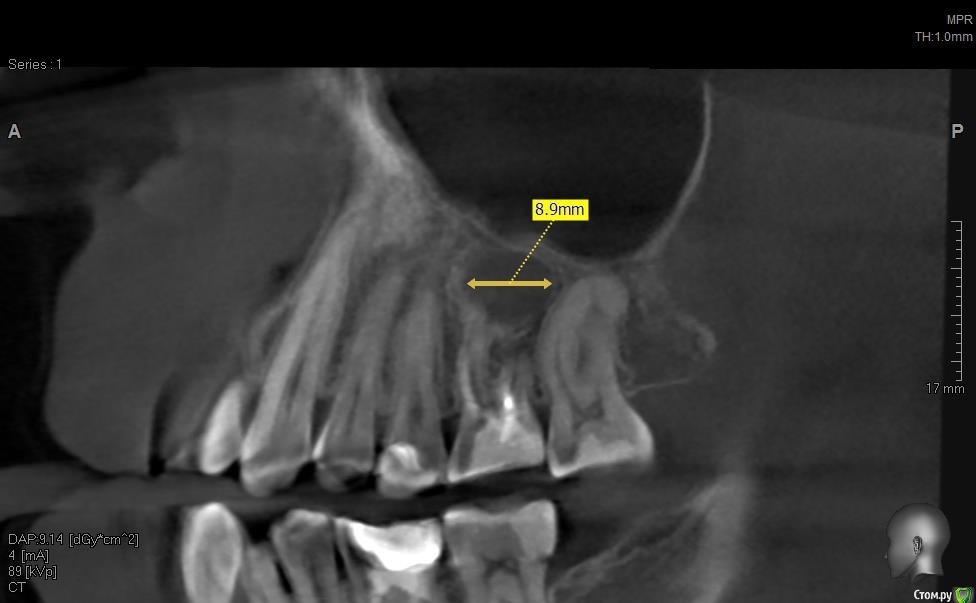

solitary Опубликовано 10 апреля, 2017 Поделиться Опубликовано 10 апреля, 2017 Доброго времени суток! Мое желание исправить прикус превратилось в ходьбу по врачам - от терапевта, до оториноларинголога и хирурга. На ОПТГ (прилагаю) ортодонту не понравилось темное пятно над верхней правой 6-кой. Т.к. хирурга у них в клинике нет, то на консультацию отправили к ортопеду-имплантологу. Предварительный диагноз - киста. Сделали КТ (скриншоты прилагаю).Диагноз подтвердили, но на всякий случай отправили к ЧЛ-хирургу. Тот с КТ от Пикассо не работает (компьютер слабый), но по моим скриншотам также считает, что это киста. Стоматолог врач-терапевт высшей категории вскрыла пломбу и увидела хорошо пролеченные каналы, плюс сделала прицельный снимок 6-ки, который кисту в зоне корня зуба не выявил (даже намека нет). Хотят отправить к оториноларингологу, так как, если верить КТ, киста у границы гайморовой пазухи и консультация ЛОР-врача будет не лишней. Хотелось бы послушать мнение опытных хирургов.-------ОПТГ http://radikal.ru/big/hq2s2k2k9uadn Ссылка на комментарий

колесников Опубликовано 10 апреля, 2017 Поделиться Опубликовано 10 апреля, 2017 Читаю и все больше удивляюсь. Место действия Москва?Удаляйте в плановом порядке,пока дно гайморовой пазухи не вскрыто кистой. В случаях схожих с вашим,рекомендую пациентам совместить удаление с одномоментной имплантацией,пока ещё условия позволяют. 2 Ссылка на комментарий

Irouil Опубликовано 10 апреля, 2017 Поделиться Опубликовано 10 апреля, 2017 Читаю и все больше удивляюсь. Место действия Москва?Удаляйте в плановом порядке,пока дно гайморовой пазухи не вскрыто кистой. В случаях схожих с вашим,рекомендую пациентам совместить удаление с одномоментной имплантацией,пока ещё условия позволяют.Там ортодонтия планируется. Надо сроки у ортодонта узнать примерные, можно консервацию провести и имплантировать за полгода до снятия системы. Ссылка на комментарий

solitary Опубликовано 11 апреля, 2017 Автор Поделиться Опубликовано 11 апреля, 2017 (изменено) Проконсультироваться с ортодонтом,будет ли смещаться 5ка,один из вариантов -отложить удаление.В случае обострения 6ки,действительно удаление с консервацией лунки.ВЧ сужена, перед установкой брекетов планировалось поставить несъемный аппарат с зацепом за 4-ки и 6-ки для расширения на зубоальвеолярном уровне. На ортопантомограмме (ОПТГ) корень правой 6-ки не вызвал у ортодонта доверия и ставить аппарат она отказалась. Без расширения ВЧ аппаратом, брекеты ставить не будут, потому что место в челюсти не хватит для всех зубов. -----------------Приблизительно так выглядит этот аппарат http://www.ortodont63.ru/upload/iblock/cfe/cfe155bbe23bf82eaa347a5307143615.jpg Изменено 11 апреля, 2017 пользователем solitary Ссылка на комментарий